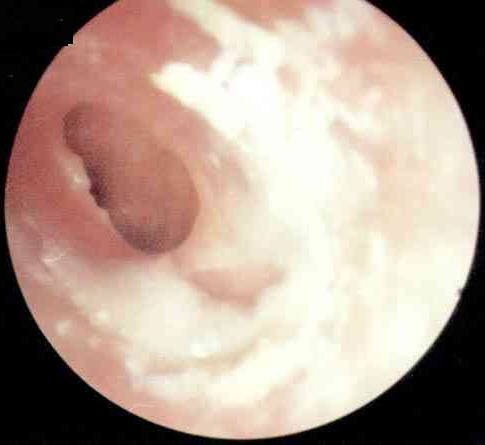

中耳炎病理图

西安中大耳鼻喉医院耳病诊疗中心张全安教授介绍,对于耳朵流脓,许多人都认为没什么了不起,是小毛病。但事实上,由于人的耳部与头颅内的脑膜很接近,中耳若感染发炎,可以通过血液循环或是通过内耳直接扩展到颅内,而引起颅内的并发症,严重时可以危及患者的生命安全。经过检查发现,刘先生属于化脓性中耳炎,病灶已侵犯到脑部造成脑脓肿从而导致头部剧烈疼痛,这个时候如果脓肿破裂则随时有生命危险。随后冯亮医生为他实施“”,有效解除了隐患。

慢性中耳炎按患病时间、病情轻重不同分为三种:单纯性,脓疡性和胆脂瘤性。它们共同的表现是均有耳流脓,反复不止,有时脓液中还混有血性分泌物;另外,有耳鸣及听力下降,如果出现并发症,会有眩晕和头痛。